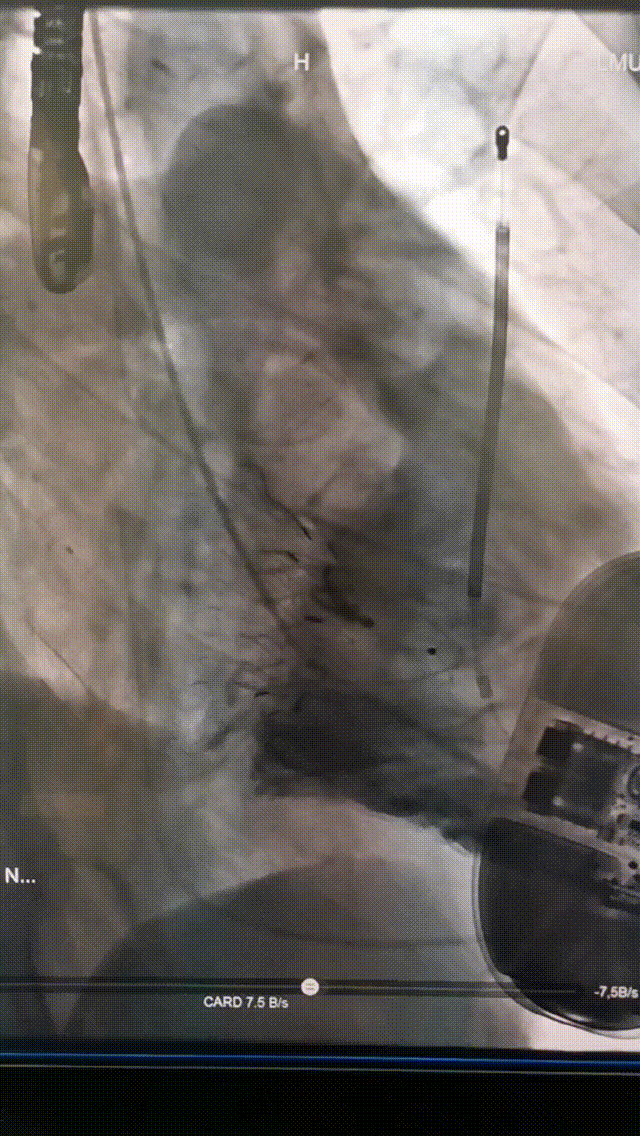

术后即刻DSA造影